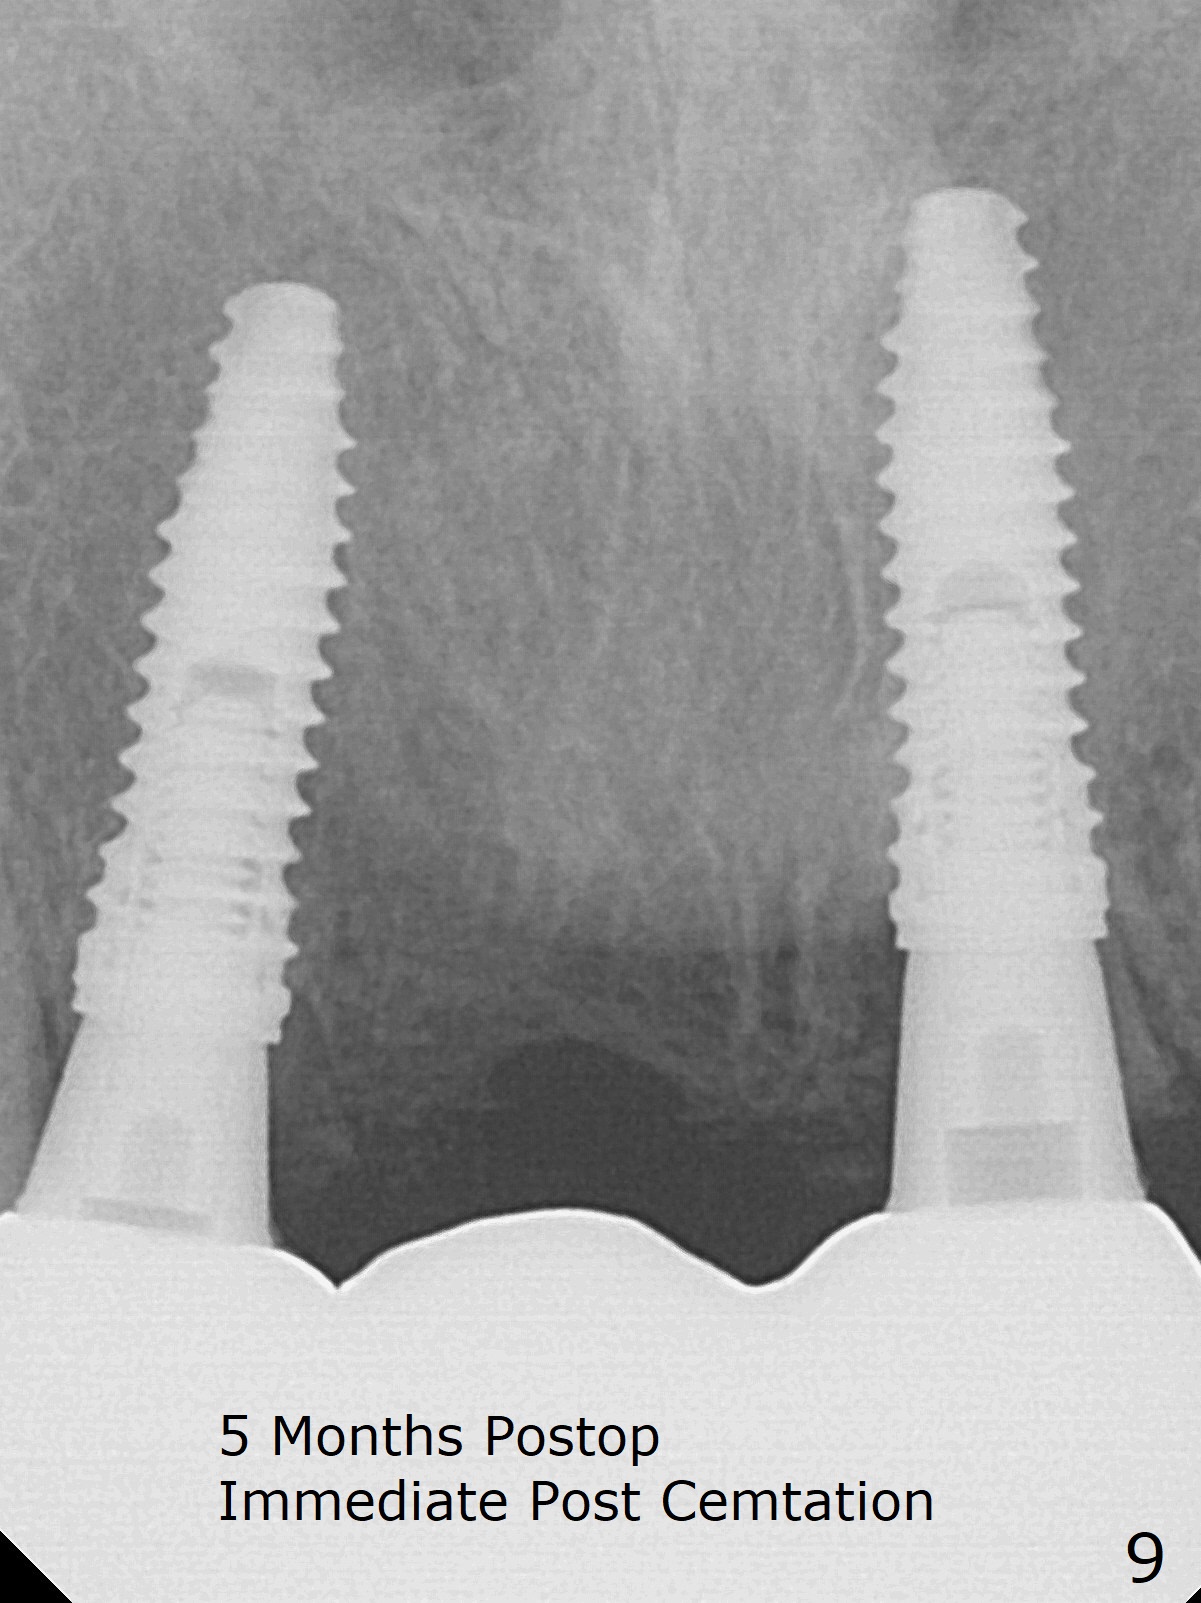

Since the pontic (Fig.1 #8) of the existing failed FPD has severe buccal concavity (*), socket shield is performed when #7 and 9 are extracted (Fig.2,3 *). Angled abutments are placed when 3.5x13 mm implants are inserted with guide. An immediate provisional FPD is fabricated. Acrylic is added to the pontic of the temporary FPD (Fig.4 arrow) to form a concave pontic gingiva (blanch)16 days postop. The patient returns 3.5 m postop with concern over temp being bulky and turning yellow. With Cetacaine and 1-0 cord, labial reducion is done for 7,9 abutments as well as 7 incisal reduction. The provisional is relined to increase 7 8 crown length. Next visit we will continue modification of temporary. Photos will be taken before and after modification (buccal and incisal views). The patient complains of occasional pain at #7. Check whether the socket shield at #7 is a culprit. In fact the implant at #7 is normal. Manipulation of the provisional does not help cosmetics much. A permanent restoration is delivered 5.5 months postop (Fig.7-9).